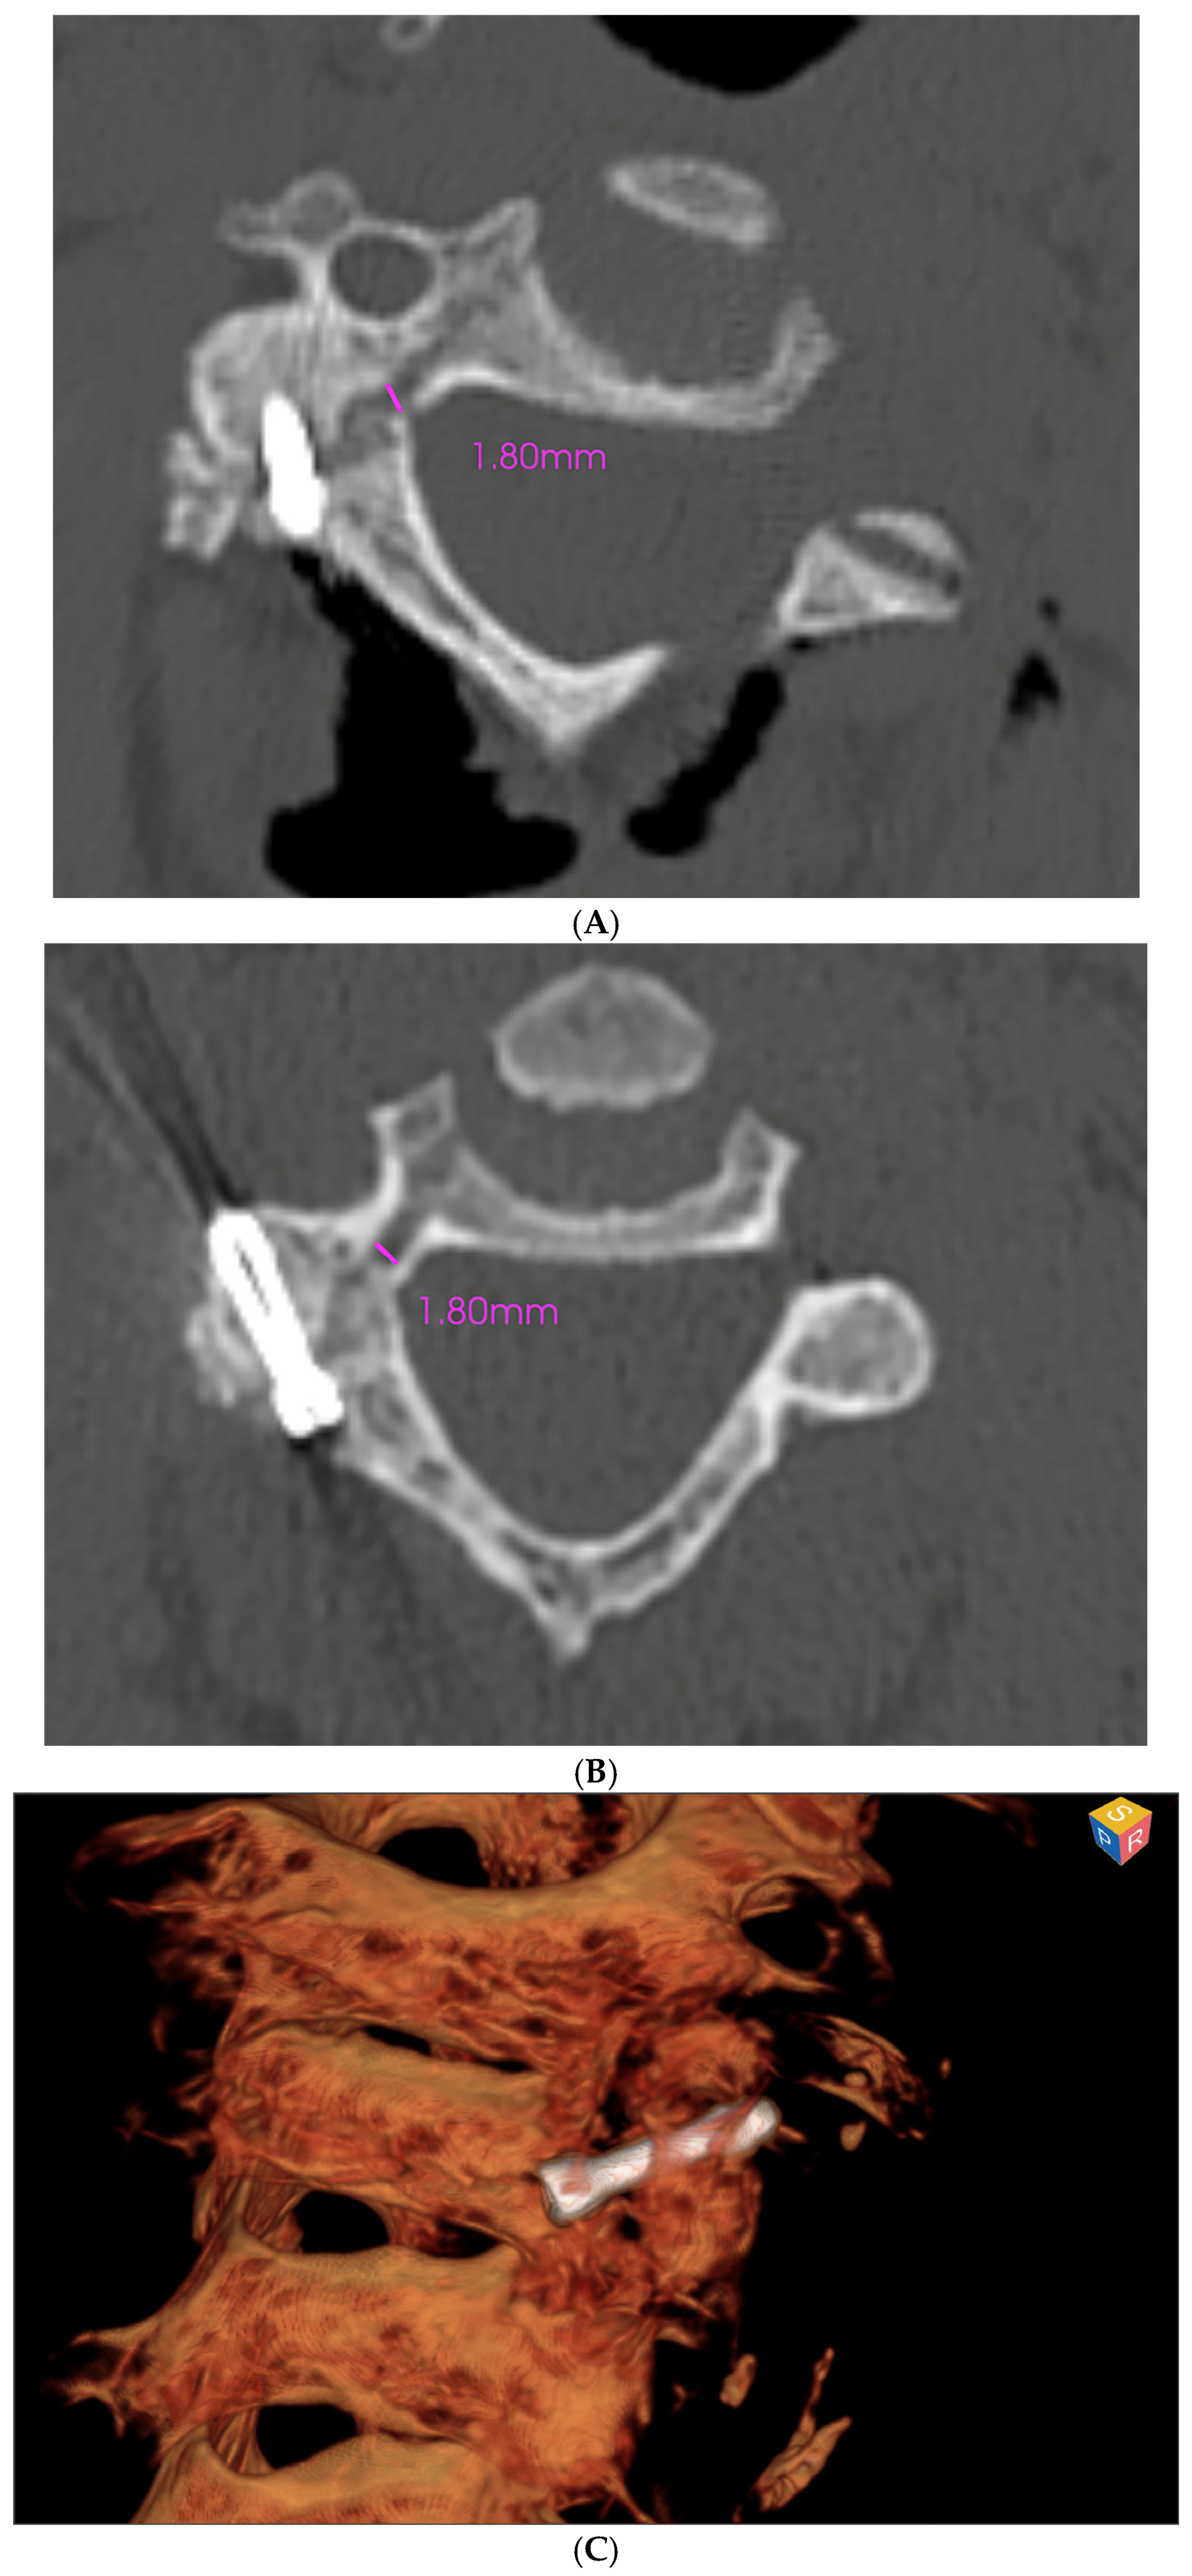

2.2. Surgical Technique

3. Results